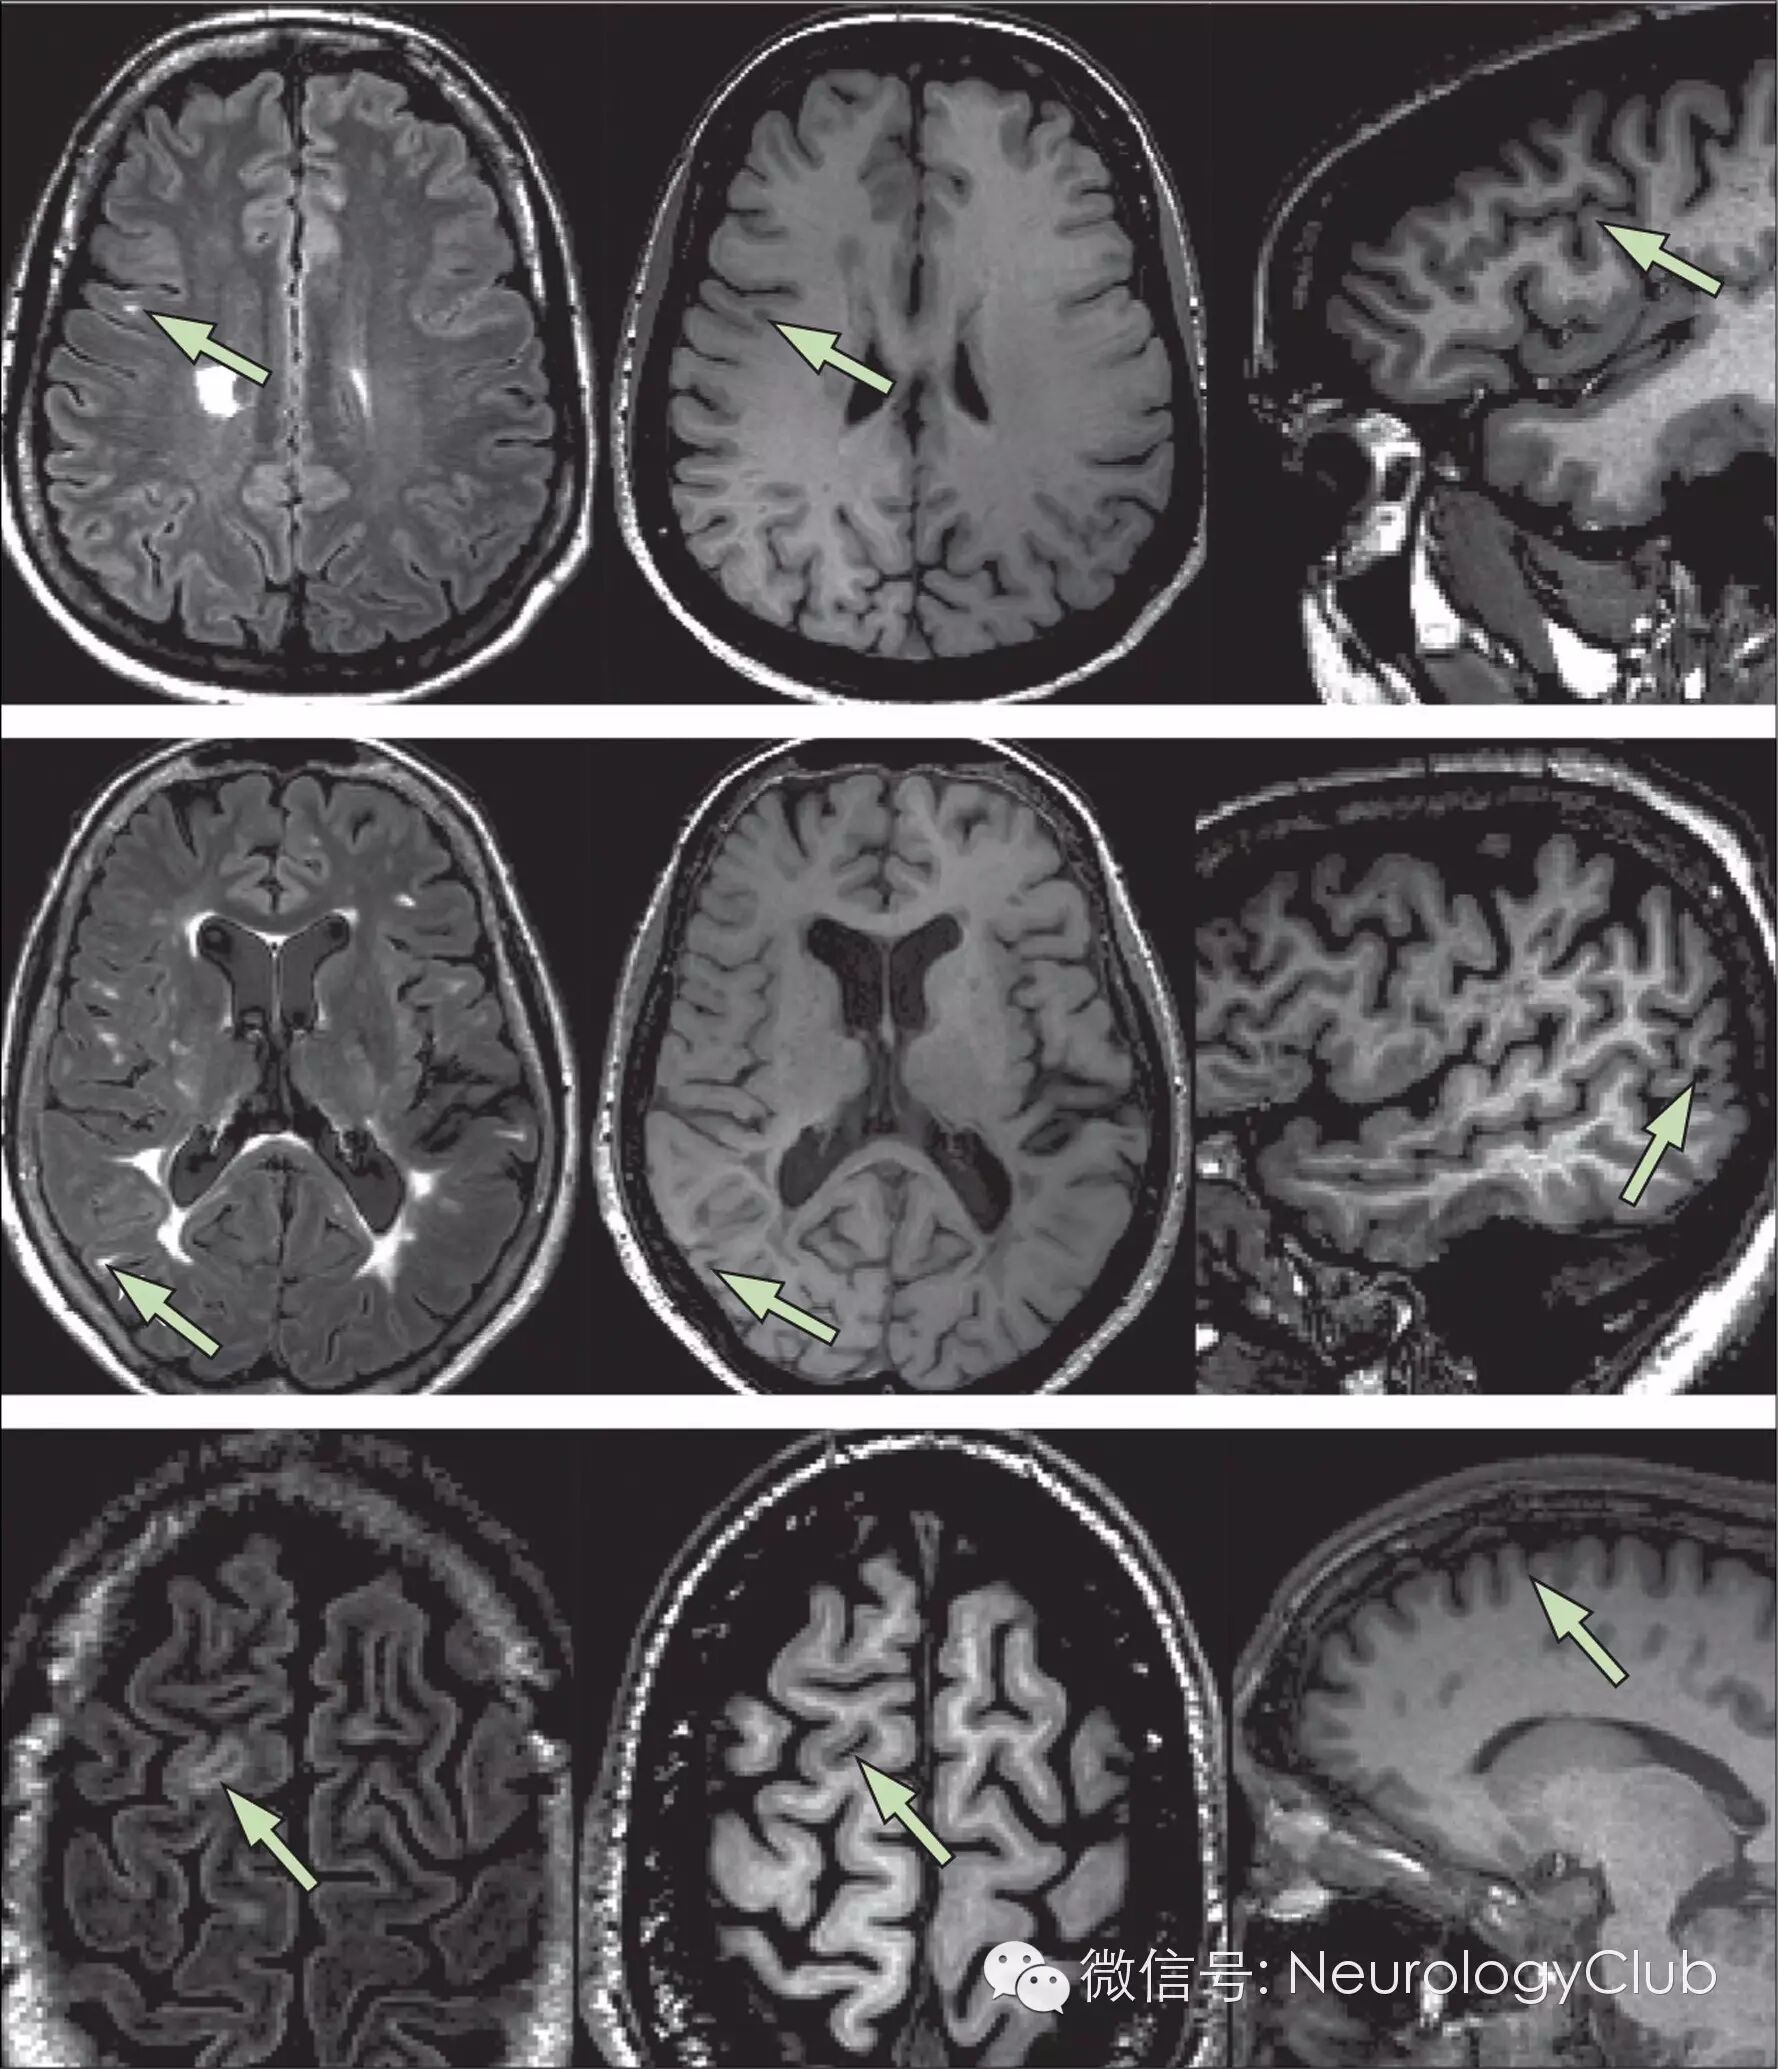

图4  MRI上病灶内中央血管的识别

[一位33岁女性MS患者在3.0T MRI上非强化FLAIR序列(水平位、矢状位和冠状位图)。多数高信号病灶内可见明显的中央血管。定义小静脉周围病灶至少需要在两个垂直面上见中央血管(放大框里的箭头)]